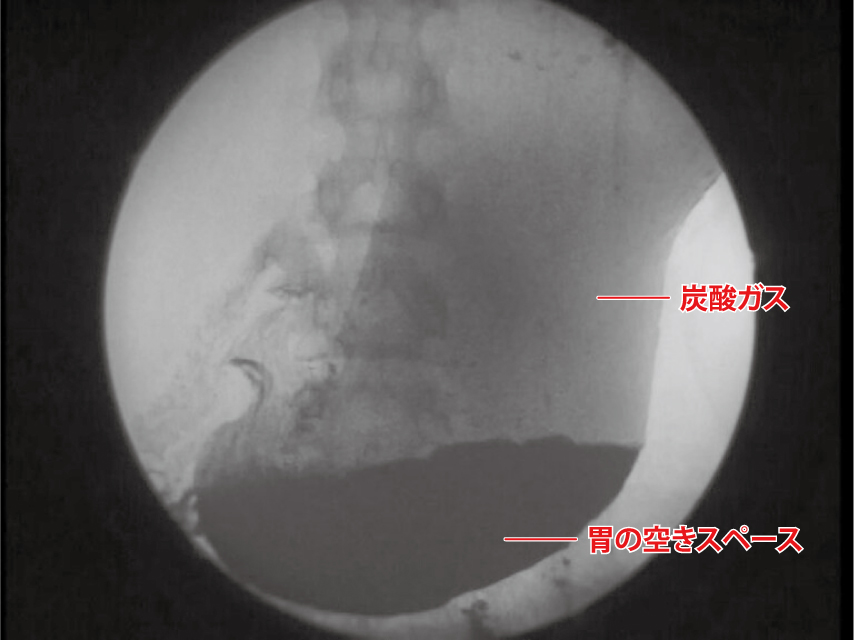

150ml飲んだとき

▲炭酸水を少量飲むと、胃が内容物を腸に送り出す「ぜん動運動」が活発になります。食べ物に備えて胃のスペースが確保されるので、食欲が増進することに。